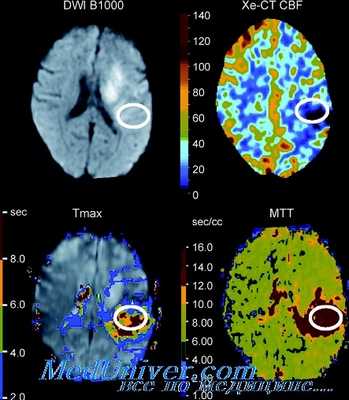

Перфузионная КТ в мониторинге регионарного мозгового кровотока

• Региональный кровоток определяется измерением первого прохода введе-ного йодированного контрастного вещества через мозг.

• Необходим высокоскоростной спиральный КТ-сканер и специальное программное обеспечение.

Преимущества:

• Обеспечивает детальный снимок.

Недостатки:

• Объем исследования ограничен общей дозой радиационной нагрузки.

• Объем контраста ограничивает возможность повторения исследования.

Специфика использования:

• Позволяет определить зоны гипоперфузии, гиперемии и анемии.

• Возможность определения зон вторичного повреждения при ЧМТ.

Диффузионно-взвешенная МРТ:

• Может быть использована для выявления местных задержек перфузии.

Перфузионная МРТ

• Измерение мозгового кровотока и объема крови после инъекции парамагнитного контраста (гадолиний-хелат).

• Показывает снижение объема крови в зонах фокальных нарушений, но результаты сложно оценить в количественном отношении, и они малоипфор-мативны при неотложных состояниях.